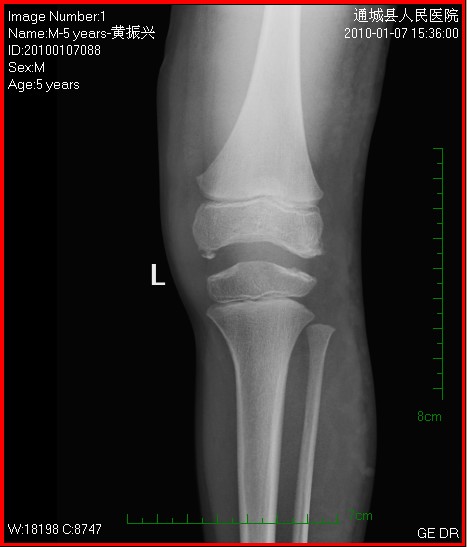

以下是引用随光逐影在2010-1-9 8:21:00的发言:[br]考虑左侧大、小腿外侧软组织内蔓状血管瘤伴左膝关节侵蚀,左侧髌骨及左侧股骨下端、胫骨上端骨骺异常发育。

以下是引用zxl51642在2010-1-9 17:29:00的发言:[br]首先要排除外敷药物等伪影,软组织血管瘤彩超没看见?[br]关节面凸凹不平,软骨及软骨下骨坏死,股骨内髁下方见碎骨片影,可能:1、首先考虑幼年型类风湿;2、股骨髁缺血性坏死,原因可能类似blount';s病机理;3、男性患儿查个尿排除尿黑酸症。